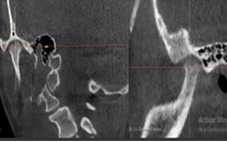

A través de los cortes tomográficos (Figura 3) se pudo observar que la rama mandibular derecha medía 43.85 mm y la izquierda 39.53 mm dando una diferencia de 4.34 mm lo que evidencia que la asimetría que presenta la paciente es a causa de la discrepancia de tamaño de las ramas mandibulares (A).

En el corte a nivel de la articulación temporomandibular izquierda se observó un aplanamiento del cóndilo con áreas de cambios osteoartríticos leves (B); en la articulación temporomandibular derecha el cóndilo se encuentra con una severa osteoartritis que muestra una imagen hipodensa a nivel condilar compatible con un quiste subcondral (C).

Diagnóstico de ATM: La paciente presenta una displasia discal sin reducción bilateral.